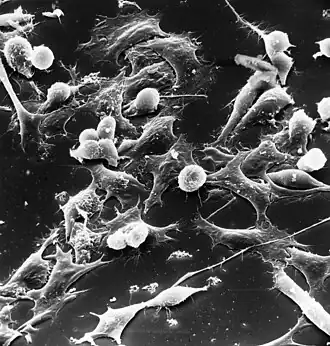

Células tumorales (las células estrelladas) de un nefroblastoma. Microscopía electrónica. | ||